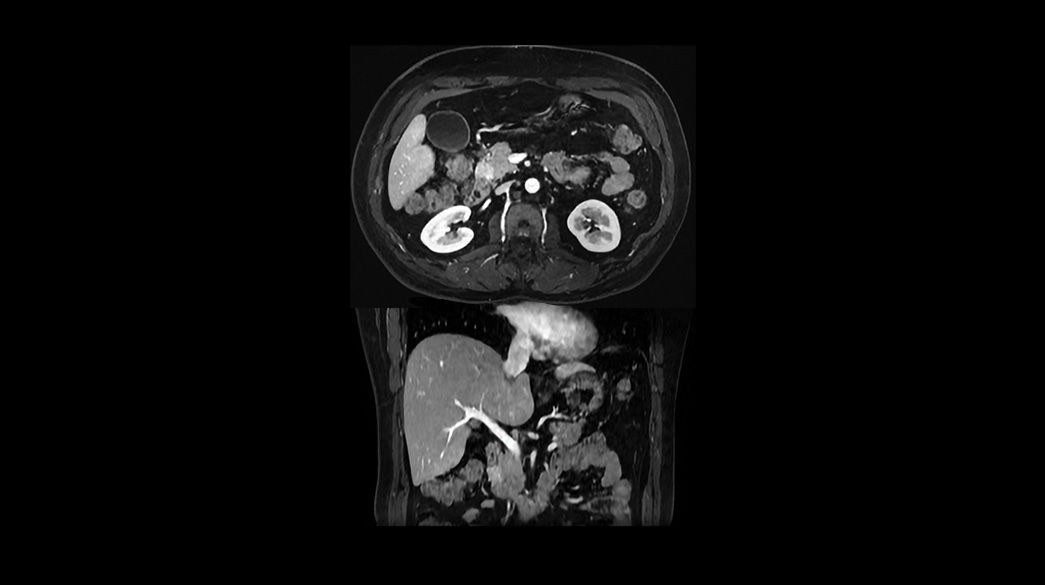

Diagnostic confidence and consistency

Precision and personalization

Ideal-IQ1040-x-585

Read case study ico-caret-right